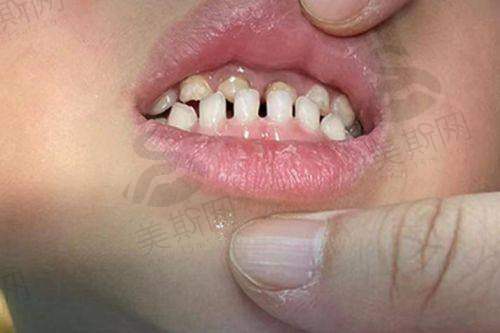

在儿童早期干预领域,他针对3 - 12岁儿童的牙颌发育问题,采用MRC肌功能矫治器、ETA矫正器等设备,结合颌骨生长改良技术,有效预防恒牙期重度错颌畸形,临床数据显示90%儿童患者可避免成年后二次矫正。对于成人骨性错颌畸形,如骨性龅牙、地包天、偏颌等,他创新融合“皮质骨切开术加速正畸”与“微种植体支抗技术”,实现牙齿精细移动,内收量可达5 - 8mm,避免传统正颌手术创伤。

针对儿童口呼吸、反颌等问题,他采用“生长改良 + 功能矫治”双管齐下策略,通过MRC肌功能矫治器训练口周肌群,结合Grace硅胶矫治器引导颌骨发育。8岁骨性反颌儿童实例中,仅12个月即实现下颌前移4.2mm,ANB角改善6°,避免成年后正颌手术,相关技术获国内自然科学基金支持。

实例2:儿童地包天早期干预

10岁男孩因“地包天、下颌前突”就诊,家长担心手术风险。张栋梁医生评估后采用“功能矫治器 + 颌位诱导”方案,通过改良式Frankel矫治器引导上颌骨发育,同时纠正不良口腔习惯。12个月后反颌解除,ANB角从 - 2°改善至3°,咬合关系修复正常,家长在社交平台分享:“孩子现在敢大笑了,张医生不仅技术好,还会用动画讲解矫正过程,孩子全程不抵触。”